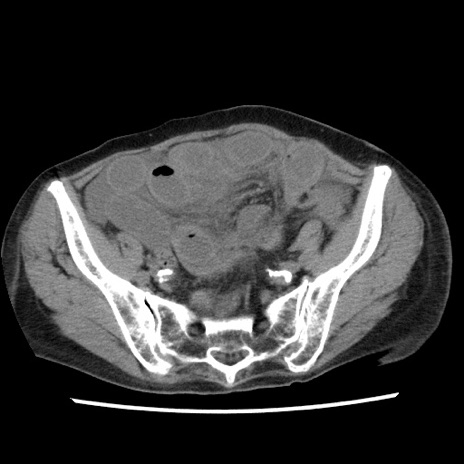

冠状断像

【症例】80歳代女性

【主訴】腹痛

【現病歴】8時間前から腹痛あり来院。

【既往歴】糖尿病、脂質異常症、子宮体癌にて子宮全摘術

【身体所見】意識清明・会話良好だが腹痛で苦悶様、全腹部にわたって反跳痛と圧痛あり

【データ】WBC 13600、CRP 0.14、LDH 224、CK 90